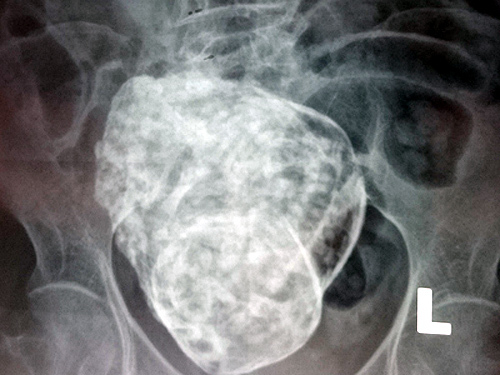

Theo người nhà, cụ bà N.T.S vào viện sáng ngày 22/3 do đau cột sống thắt lưng và vùng hạ vị. Qua thăm khám và chụp X quang, các bác sĩ của BV phát hiện vùng tiểu khung có khung xương thai nhi (gồm hộp sọ, cột sống, các xương sườn và xương đùi) và được chẩn đoán: có thai hết lưu trong ổ bụng. Được biết, cụ bà đã mãn kinh từ năm 49 tuổi, bà có 4 lần sinh con, 1 lần sẩy thai và hiện sống với người con trai út gần 50 tuổi.

Phim chụp X-Q cho thấy khối thai đá trong ổ bụng của cụ bà N.T.S |